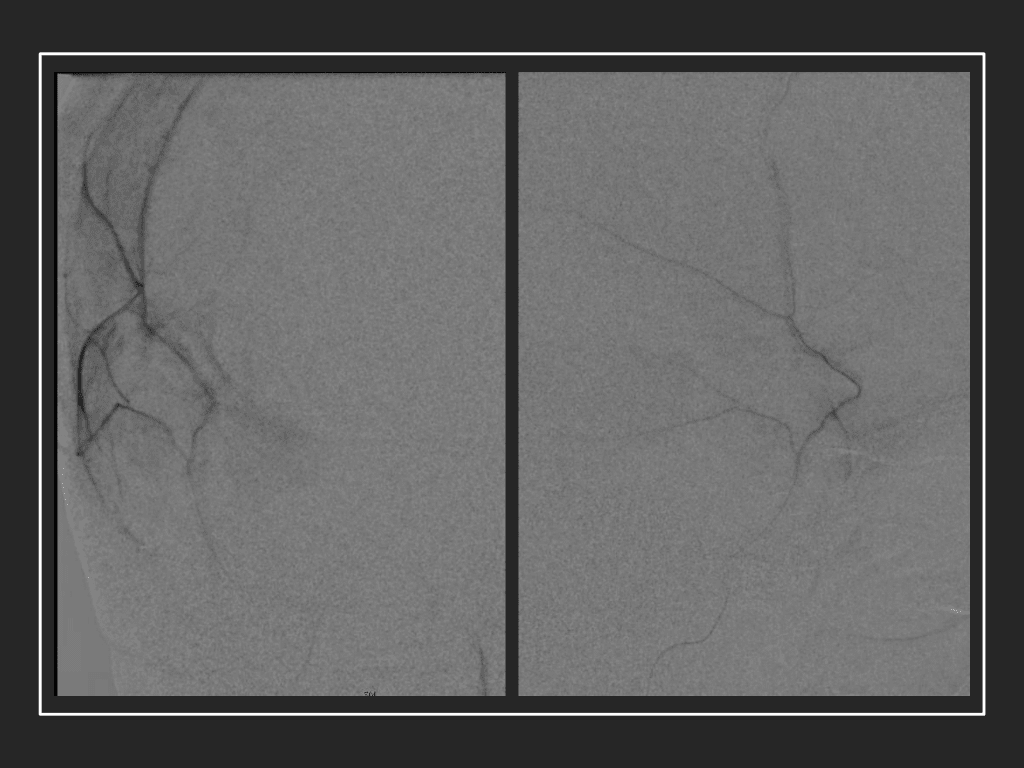

A woman in her 80s developed mild dizziness and headache following incidental trauma working in her garage one day. She presented several weeks later to the ER and was diagnosed with bilateral subdural hematomas, which were initially managed with observation, low dose Decadron, considering the mildness of symptoms, advanced age, and history of CLL with thrombocyptopenia (<100k). Over the next 4 weeks, the collections remained relatively stable with evidence of slight growth (10 to 12 mm thickness, and 2 mm right to left shift) on NCT (Figure 1. A and B).

Figure 1. A) 6 weeks post mild trauma B) 4 weeks post mild trauma demonstrates stable subacute subdural collections with mild growth and sulcal effacement.